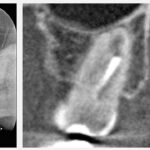

3ヶ月前に、右上奥歯のズキズキとした痛みを主訴に、近くのかかりつけ歯科にて根管治療(抜髄)を開始しました。週1回、10回程度治療を続けていましたが、痛みは引かないどころか強くなる日もあり、ご自身で根管治療について調べたとのことです。その結果、ラバーダム防湿が重要と知ったものの治療を受ける際にはラバーダムが使われておらず、精密な治療を求めて当院を受診されました。

3ヶ月ぐらい前にズキズキとした痛みがあり、近くの歯医者さんで神経を取る処置が必要と言われ、治療を開始しました。初めは「4〜5回ぐらいで終わると思う」と言われていましたが、痛みがずっと変わらず、現在までに10回程度治療を続けています。それでも治らないため、ネットで根管治療について調べて、髙井歯科クリニックに来させていただきました。

ありがとうございます。根管自体はシンプルな形態ですので、おそらく1回で治療は完了できるかと思います。